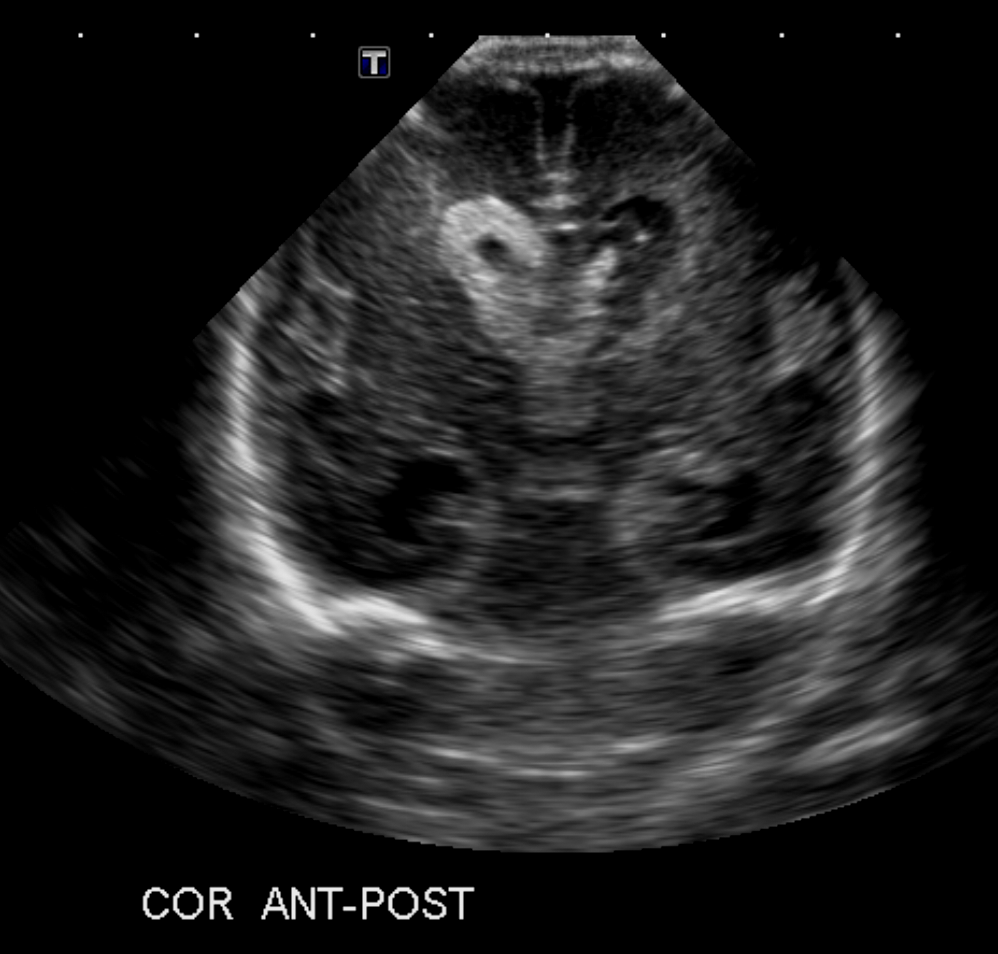

Info Images Findings Impression Reco/Acuity Case Images View Images / Launch Visage Case Notes History Full term infant. We are asked to evaluate posterior fossa cyst. Exam Gray scale and Doppler Ultrasonographic examination of the head. Prior Study N/A Dicom View Reference Material

Section 1 Submit Findings Case149 Findings Brain The brain is immature. Yes No There is under-sulcation and open sylvian fissures. Yes No There is/are multiple hypoechoic areas in the periventricular white matter. Yes No There is/are multiple hyperechoic areas in the periventricular white matter. Yes No There is diffuse cerebral edema with diffusely increased echogenicity of the brain parenchyma and loss of grey white matter differentiation. Yes No The thalami/basal ganglia are hypoechoic. Yes No There is periventricular calcification. Yes No There is intra-parenchymal calcification. Yes No CSF spaces/ventricular system There is a prominence of the extra axial fluid spaces. Yes No There are debris/septations in the extra axial fluid spaces. Yes No There are debris/septations in the ventricles. Yes No There is a subdural collection on the right/left side. Yes No There is prominence of the ventricular system. Yes No There is an asymmetry of the ventricular system. Yes No There is a cavum septum pellucidum. Yes No There is a midline shift towards right/left. Yes No The choroid plexus is bulky/lobulated. Yes No There is a choroid plexus cyst measuring… Yes No There are debris/clots in the occipital horn. Yes No There is a posterior fossa cyst measuring… Yes No The tentorium is elevated/depressed. Yes No The lateral ventricle/s are dilated. Yes No The third ventricle is dilated. Yes No The 4th ventricle is dilated. Yes No There are pseudo cysts. Yes No Germinal matrix hemorrhage (Only in the premature infants): Please do not answer if the patient is a full term. There is a germinal matrix hemorrhage, consistent with a grade I hemorrhage. Yes No There is an intraventricular extension consistent with a grade II hemorrhage. Yes No There is an intraventricular extension with the dilatation of ventricles, consistent with a grade III hemorrhage. Yes No There is an intra-parenchymal extension, consistent with grade IV hemorrhage. Yes No On color Doppler examination, the Resistive index in the anterior cerebral artery is… There is a loss of the diastolic flow on the Doppler exam. Yes No There is altered vascularity on Doppler imaging. Yes No There is an AVM in the region of… Yes No